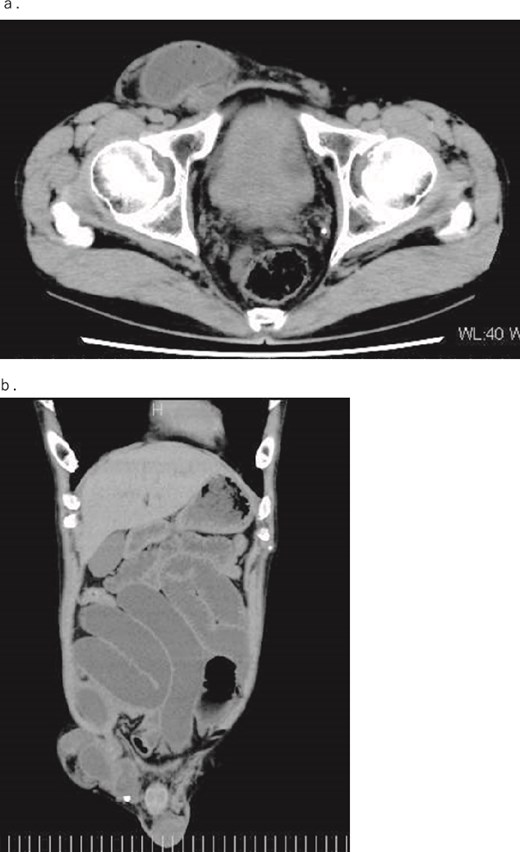

A 54-year-old, normally healthy patient had been experiencing abdominal pain for approximately 6 hours before visiting our hospital. Computed tomography (CT) revealed an incarcerated right inguinal hernia (Fig. 1); therefore, he visited our hospital. At the time of his visit, the pain had disappeared, as had the bulge in his groin. However, he still felt abdominal fullness. A repeat CT scan revealed that part of the prolapsed intestine remained in the groin. Therefore, the patient was admitted immediately and underwent emergency surgery on the same day. Laparoscopic surgery was performed under general anesthesia. Intraperitoneal findings did not confirm intestinal prolapse; therefore, right inguinal hernia repair using a transabdominal preperitoneal (TAPP) technique with placement of a 3DMax Light Mesh (Bard) was conducted. Because the patient also had an incarcerated inguinal hernia, a detailed examination of the digestive tract revealed a diverticulum on the opposite side of the mesentery, 70 cm from the terminal ileum, and dilation of the oral intestine was observed starting from this site (Fig. 2). Considering the possibility that the Meckel’s diverticulum indicated an incarcerated inguinal hernia, the intestine was elevated outside the abdominal cavity through a small abdominal incision to keep away from the mesh. The diverticulum was resected with a Powered ECHELON FLEX 3000 (ETHICON), and the stapler line was buried with a seromuscular suture to complete the surgery. Pathological examination of the diverticulum revealed ectopic gastric mucosa, although no malignancy was noted.

(a) Axial and (b) coronal contrast-enhanced CT images. The images show dilation of the intestine due to incarceration of a right inguinal hernia.